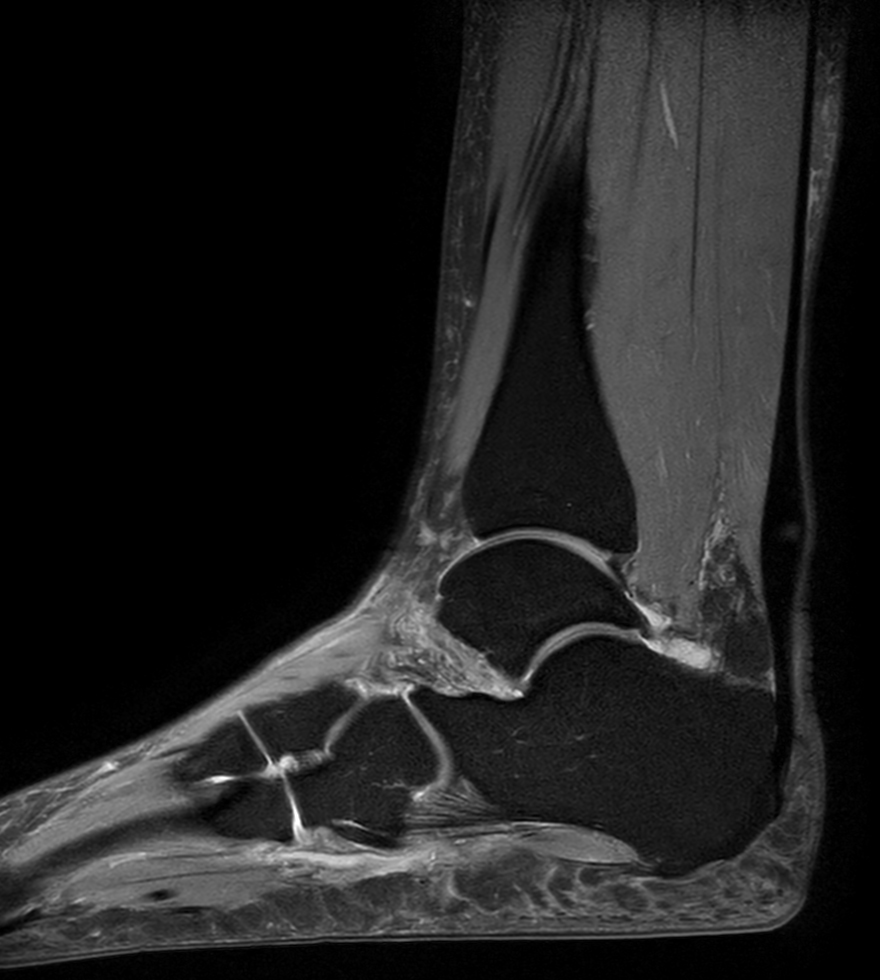

Imaging with the dS 16ch FootAnkle coil

General Hospital Sint Blasius, Dendermonde, Belgium

Patient who was referred for imaging of the achilles tendon